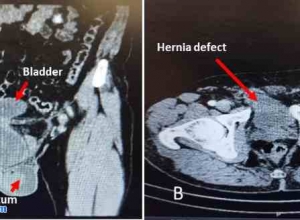

膀胱结石和缺血性肠袢合并腹股沟滑动性膀胱